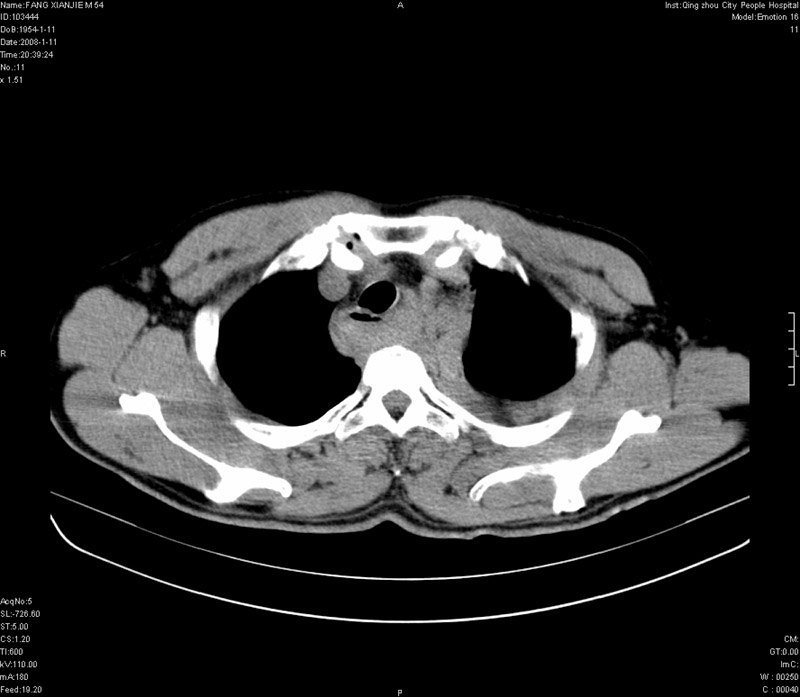

男性,40岁。胸部被车压伤伴胸痛1小时来院就诊。检查:一般情况尚可,血压110/80,胸部及上腹部压痛。结果在三天后公布。骨窗在横断位、冠矢状显示肋骨、胸椎、和胸骨未见骨折征象。

病人很危险啊,考虑胸主动脉破裂出血。

1)考虑为:胸主动脉破裂伴纵隔血肿,左侧胸腔积液(血)。2)胸骨柄骨折。

纵隔血肿,大血管破裂?左侧胸腔积血,胸骨柄骨折,冠状位示双侧第三肋骨折.

ct11308:胸部外伤1小时(证实病例) (2008-1-13 16:2)结果如下:病人入院后两小时后症状加重,8小时后在征得病人家属同意做了ct增强扫描。如下图。最终临床诊断:外伤性胸主动脉破裂并纵隔内血肿。由于有运动性伪影,胸骨在矢状面重建的图像似有骨折征,这是一种假象,我们称之为“假骨折”,这在多层ct重建中经常性遇到,必要时要结合横断图像鉴别之。现在,病人的一般情况较差,是否要手术家属尚有争议,如果手术修补,难度较大,需要专门预定制作固定支架。

当然,对于该病例,其它非重要的诊断还有:右侧少量气胸;左侧胸腔积液;左侧轻度肺挫裂伤。对于纵隔内血肿,我们曾经遇到过多例,也有怀疑主动脉的破裂,但是,均未得到具体出血部位的明确诊断。